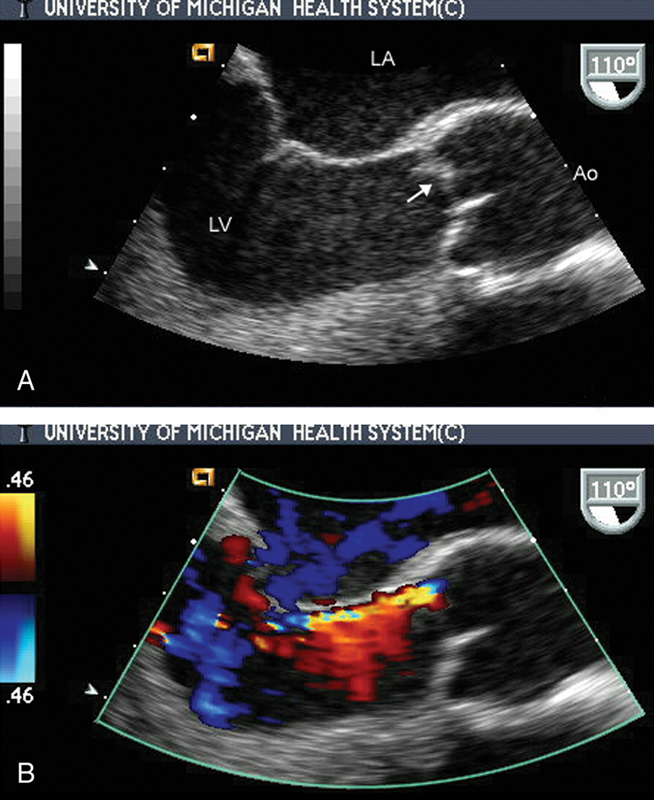

فحوصات تشخيصية لبعض امراض القلب والشرايين التاجية